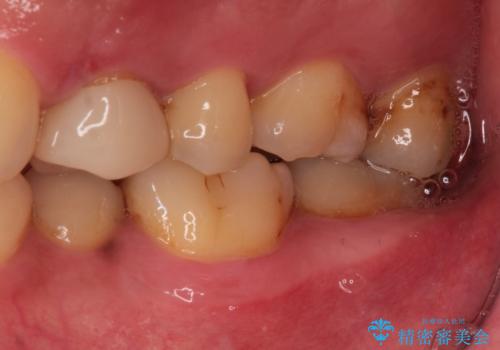

- 定期健診にて虫歯が見つかった患者さんです。他院で保険治療(CR、プラスチック)したところとまだ処置されていないところが虫歯になっていました。

セラミックインレーで治療しました。

以前保険治療で治したところが再び虫歯になっていました。保険治療で使用される材料は主にプラスチックなので必ず劣化がおきます。再治療のリスクを減らすために、セラッミックインレーで治療を行いました。セラミックインレーには劣化がほとんどありません。当院ではシリコンで型取りを行っているので、適合が良い被せものが出来き再治療のリスクを減らすことが出来ます。